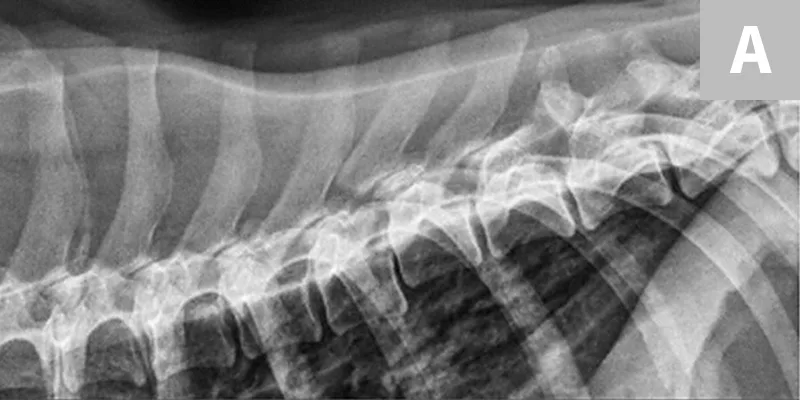

Survey radiographs of the vertebral column should be obtained, as well as chest and abdominal radiographs to assess for concurrent injuries. Horizontal beam radiographs are strongly preferred for obtaining ventrodorsal views of the vertebral column, as they do not require the patient to be moved out of lateral recumbency, which could further compromise the integrity of the vertebral column. Although sufficient for diagnosing significantly displaced vertebral fractures and luxations, radiographs are not adequate for predicting the degree of spinal cord injury or assessing the degree of vertebral instability (Figure 1 and Figure 2).

Figure 1

Lateral radiograph of a dog following unknown trauma. There is a complete oblique fracture (arrow) of the L6 vertebral body and luxation of the L6-L7 articular processes, with severe cranioventral displacement of the caudal segment. Despite the degree of displacement, this patient retained voluntary movement in both pelvic limbs on initial examination and made a functional recovery following reduction and stabilization of the fracture/luxation and 8 weeks of crate confinement.